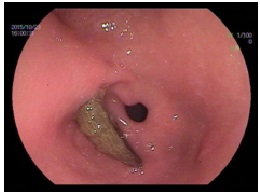

义齿,也就是俗称的假牙。很多老年朋友都会佩戴活动假牙,能够随时摘下来,由于制作方便、价格低廉,早些年非常受欢迎。但是吃一些粘的东西,比如之前说的粽子,还有年糕、糍粑、汤圆、奶糖,都会把假牙粘下来,一个不留神就咽下去了。假牙旁边一般都有几根锐利的金属丝,是用来固定假牙的,咽下去之后很容易划伤食管,甚至划破血管引起大出血,非常危险。因此建议老年朋友们,如果口腔状况能够接受固定的义齿,最好选择固定的,当然也还要听取口腔科专业的意见。

图(1)食管被假牙划出的伤口,白色柱状物是医师缝合伤口所用的钛夹尾部。后图是取出的假牙